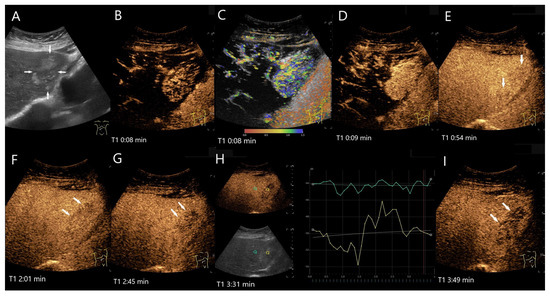

Figure 5.

FNH/nodular regenerative hyperplasia newly diagnosed in follow-up care after colon carcinoma and adjuvant chemotherapy with capecitabine and irinotecan. Initially, the lesions with a size up to 30 mm showed a wheel-spoke-like homogeneous hyperenhancement in the AP with isoenhancement in the PVP and LP. Over time, however, hypoenhancement developed in the LP. The images show the lesions three years after the initial diagnosis: the lesions (between the markings) are slightly larger (A). CEUS (B) and parametric imaging (C) show a typical wheel-spoke-like enhancement. In parametric imaging (C), the time of enhancement is displayed in different colors. The lesion is homogeneously hyperenhanced in the AP, a central scar is visible (D). In the LP, the lesions (arrows) are hypoenhanced with emphasis on the central parts (E,F). These lesions were, therefore, not clearly classifiable as benign, particularly in a patient with a history of colon carcinoma. A US-guided biopsy is performed. This revealed findings compatible with FNH and no evidence of metastases.